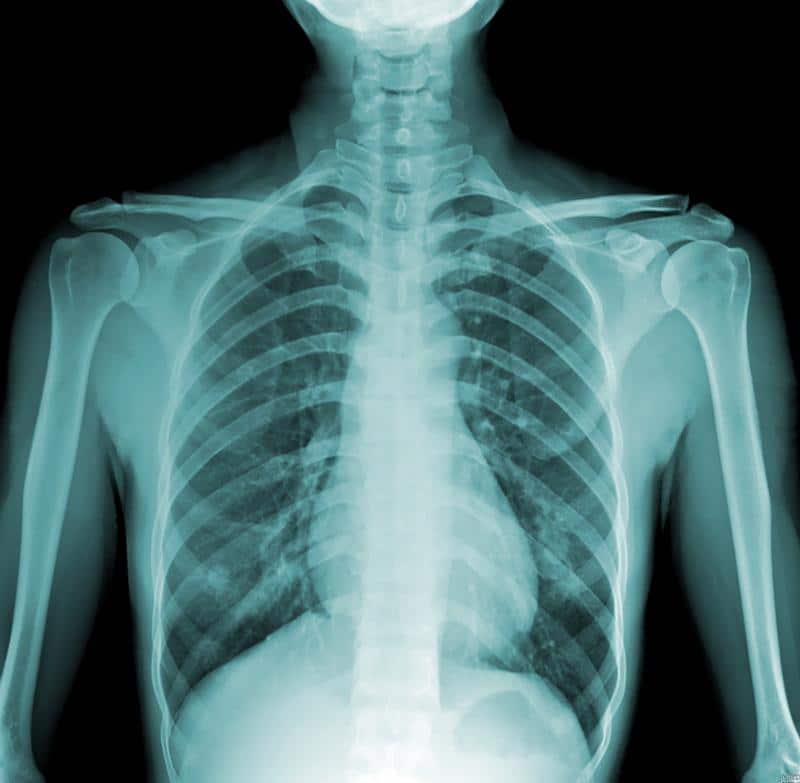

Этапы проведения рентгенографии

После подготовки пациента к рентгенографическому исследованию, человек подходит к аппарату, а медицинская сестра прижимает его таз и плечи к рентгеновской пластине. Если медсестры нет рядом, помочь пациенту может врач-рентгенолог. Во время получения снимка аппаратом, пациент не ощущает боли, но может почувствовать металлический привкус во рту.

Часто врач делает рентген грудной клетки в двух проекциях: боковой и прямой. При создании прямой проекции пациент стоит лицом к рентгеновской пластине, а в боковой проекции – поворачивается боком и поднимает руки. Рентгеновская пластина имеет холодную металлическую поверхность, что может вызывать некоторые неудобства. Температура в кабинете обычно составляет около 15-18 градусов.

Существуют ситуации, когда пациент не может самостоятельно стоять во время получения цифрового изображения. Это может быть связано с заболеваниями опорно-двигательного аппарата, суставов, травмами нижних конечностей, а также с патологиями сердечно-сосудистой системы и органов дыхания. В таких случаях пациента укладывают на специальный стол, где необходимо сохранять полную неподвижность.

Во время рентгеновского сканирования пациент должен задержать дыхание. Обычно врач или медсестра сообщают, когда нужно задержать дыхание, и когда можно выдохнуть. Это необходимо, так как движение диафрагмы и легких во время дыхания может привести к нечетким и смазанным снимкам.